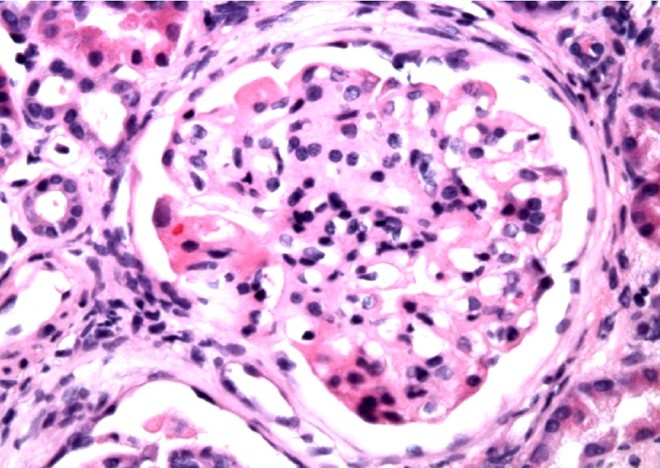

PT is a 56-year old woman with no significant medical history who presents with 2 months of LE swelling, nocturia and foamy urine

On exam, BP 138/76, periorbital edema, 3+ pitting edema of LE

Laboratory studies: Cr 1.3, TC 556, Albumin 1.8, Ur Protein: Cr ratio 13, C3 135, C4 38

HIV, HBV, HCV, ANA all negative

IgM deposition noted in histologic sample below. What is her diagnosis and treatment?

Focal segmental glomerulosclerosis:

Histology:

Light microscopy:

- Mesangial cell proliferation

- Focal process: not all glomeruli involved

- Segmental process: only tufts involved

- Trichrome stain: expansion of mesangium